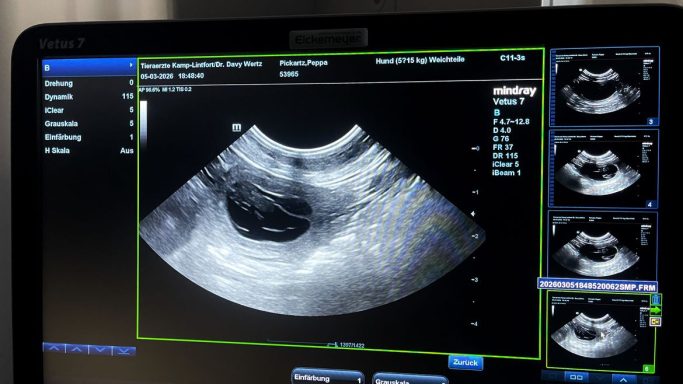

Ultraschall

Am 24. Tag nach der Bedeckung mit Anderl, waren wir beim Ultraschall mit Peppa um zu kontrollieren ob sie tragend ist und mit den Welpen alles in Ordnung zu sein scheint. Wir haben definitiv eine Trächtigkeit von Peppa gesehen und bereits Herzschläge gehört. Wieviele es werden ? Bleibt noch ein Rätsel bis zum Röntgen... noch ist sie schön schlank und sportlich...